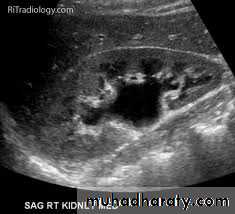

Ultrasound findings

1-Dilatation of the P.C.S. appears as multilocular fluid collection within central echo complex.

-With more severe distention, dilated calyces appear as

Multiple cysts but communicating with each other unlike true cysts.

2-Stones larger than 5mm are easily seen on US but smaller ones may be missed.

-They produce intense echoes (hyperechoic) and cast acoustic shadows.